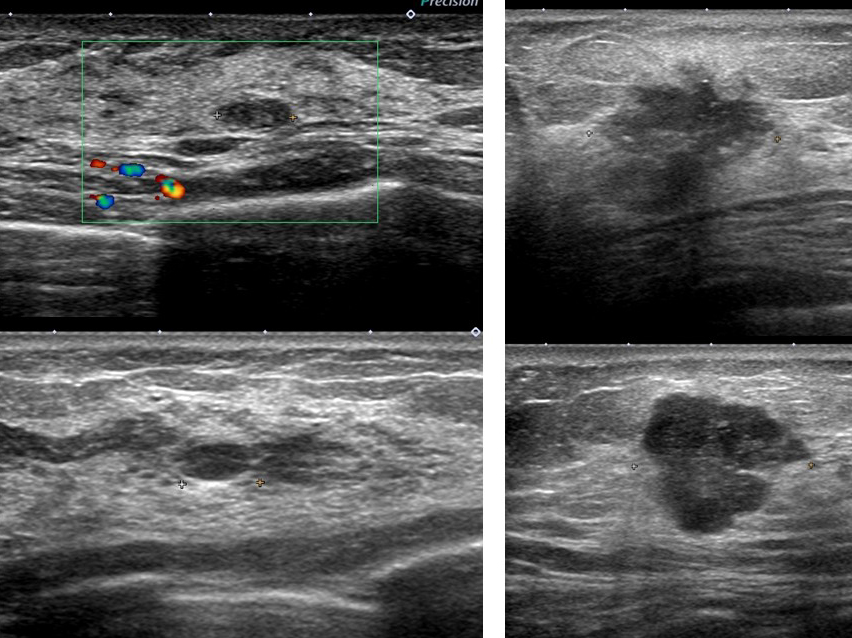

線維腺腫っぽく見えても癌 case.2

同様に左も癌です。

線維腺腫っぽく見えても癌 case.3

これなんかも(左)癌なのだから、やはり「なのは」さんの所見を「線維腺腫だ!間違いない」などというのが如何に無知なことか!

典型的な「線維腺腫(実際に生検で線維腺腫と確認)」と典型的な癌「私のcat.7」を提示します。

左と右、どちらが線維腺腫でどちらが癌なのか?当ててください(皆さんなら簡単ですね? 引っかけはありません)

このくらい典型(私cat. 2)ならば画像だけで「線維腺腫で大丈夫です」と言えるのです。

♯逆にこれくらい典型(私cat. 7)ならば画像だけで癌と言い切ってもいいでしょう。